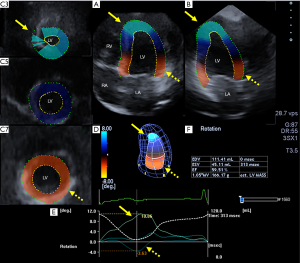

3DSTE studies were performed with the same Toshiba ArtidaTM echocardiography equipment (Toshiba, Tokyo, Japan) with a 1–4 MHz matrix phased-array PST-25SX transducer (5). Following 3D data collections within a single breath-hold from an apical window, the stored echocardiographic data were exported to a separate workstation for off-line analysis, where chamber quantification was performed using 3D Wall Motion Tracking software version 2.7 (Toshiba Medical Systems). Following definition of mitral annular edges and apex in apical two- (AP2CH) and four-chamber (AP4CH) views, endocardial border of the LV cavity was automatically detected by the software in 3D. Curves were generated by the software for quantification of 3DSTE-derived global peak apical and basal LV rotations and LV twist (Figure 1).

Routine two-dimensional echocardiographic data are presented in Table 2. None of the subjects have grade ≥1 valvular regurgitation or stenosis. During 3DSTE, basal LV rotation proved to be −3.24±2.02 degree, while apical LV rotation was 9.08±3.04 degree, therefore LV twist was 11.70±6.80 degree.